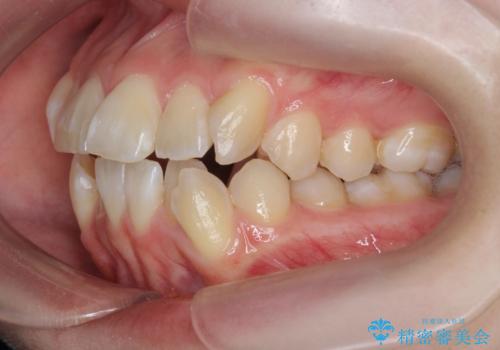

突き出た前歯を治したい 小臼歯抜歯+マルチブラケット矯正

- 突き出て、気になる前歯の角度の改善を求めて来院されました。

前歯の角度を改善するために小臼歯4本の抜歯を行いワイヤー マルチブラケットを用いて、しっかりと前歯の角度を改善する治療計画としました。